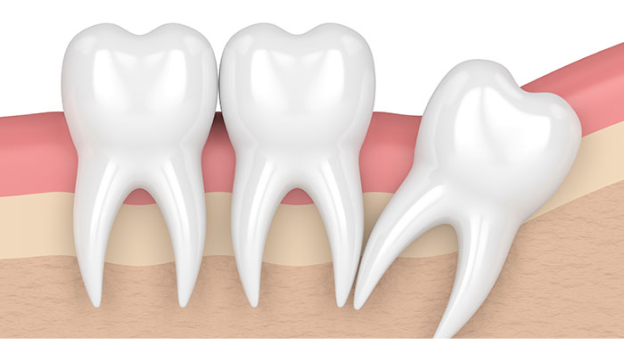

옆으로 누워서 자란 사랑니

사랑니가 누워서 자라면 바로 앞쪽 어금니 뿌리를 압박해 염증 등의 문제를 일으키거나 앞쪽 어금니와의 사이에 음식물이 잘 끼게 되어 충치와 염증을 유발할 수 있습니다.